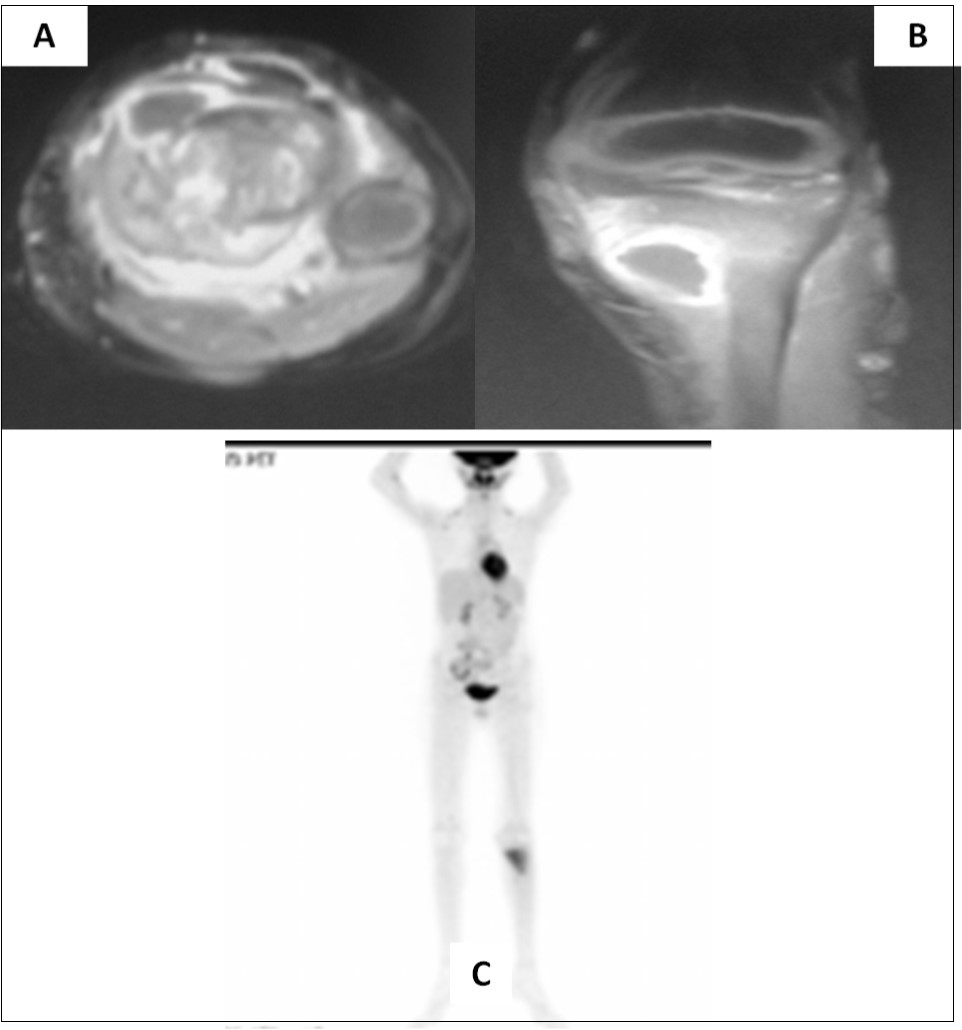

Two and half years after completion of therapy (just over 3 years from initial diagnosis), the child presented with pain in the left lower limb following a trivial injury. Local radiograph showed a large lytic/sclerotic lesion in the proximal left tibia. MRI of the left lower extremity (Figure 2A-B) confirmed the presence of this lytic/sclerotic lesion arising from the proximal tibial metaphysis with significant invasion of the adjacent soft tissues. The lesion was isointense on T1-weighted images, heterogeneously hypointense on T2-weighted images, hyperintense on STIR images with moderate post-contrast enhancement. Whole-body 18-F-fluoro-deoxy-glucose positron emission tomography/computed tomography (FDG-PET/CT) showed increased radiotracer uptake limited to the mass lesion in the proximal left tibia with a maximum standardized uptake value (SUVmax) of 6.28 suggestive of localized metabolically active tumor. There were no other areas of abnormal tracer uptake anywhere in the body ruling out disseminated disease (Figure 2C). Neuraxial imaging at this time did not reveal any local recurrence in the posterior fossa or leptomeninges confirming that the index cancer was controlled. The differential diagnosis was between second primary bone neoplasm with extensive soft tissue component versus solitary metastasis from medulloblastoma.

Figure 2.Axial (A) and coronal (B) MRI sections of left proximal tibia showing a large soft tissue component in addition to the lytic/sclerotic bony lesion. Whole body FDG-PET/CT showing increased tracer uptake localized to this lesion (C) with no significant abnormal uptake elsewhere in the body